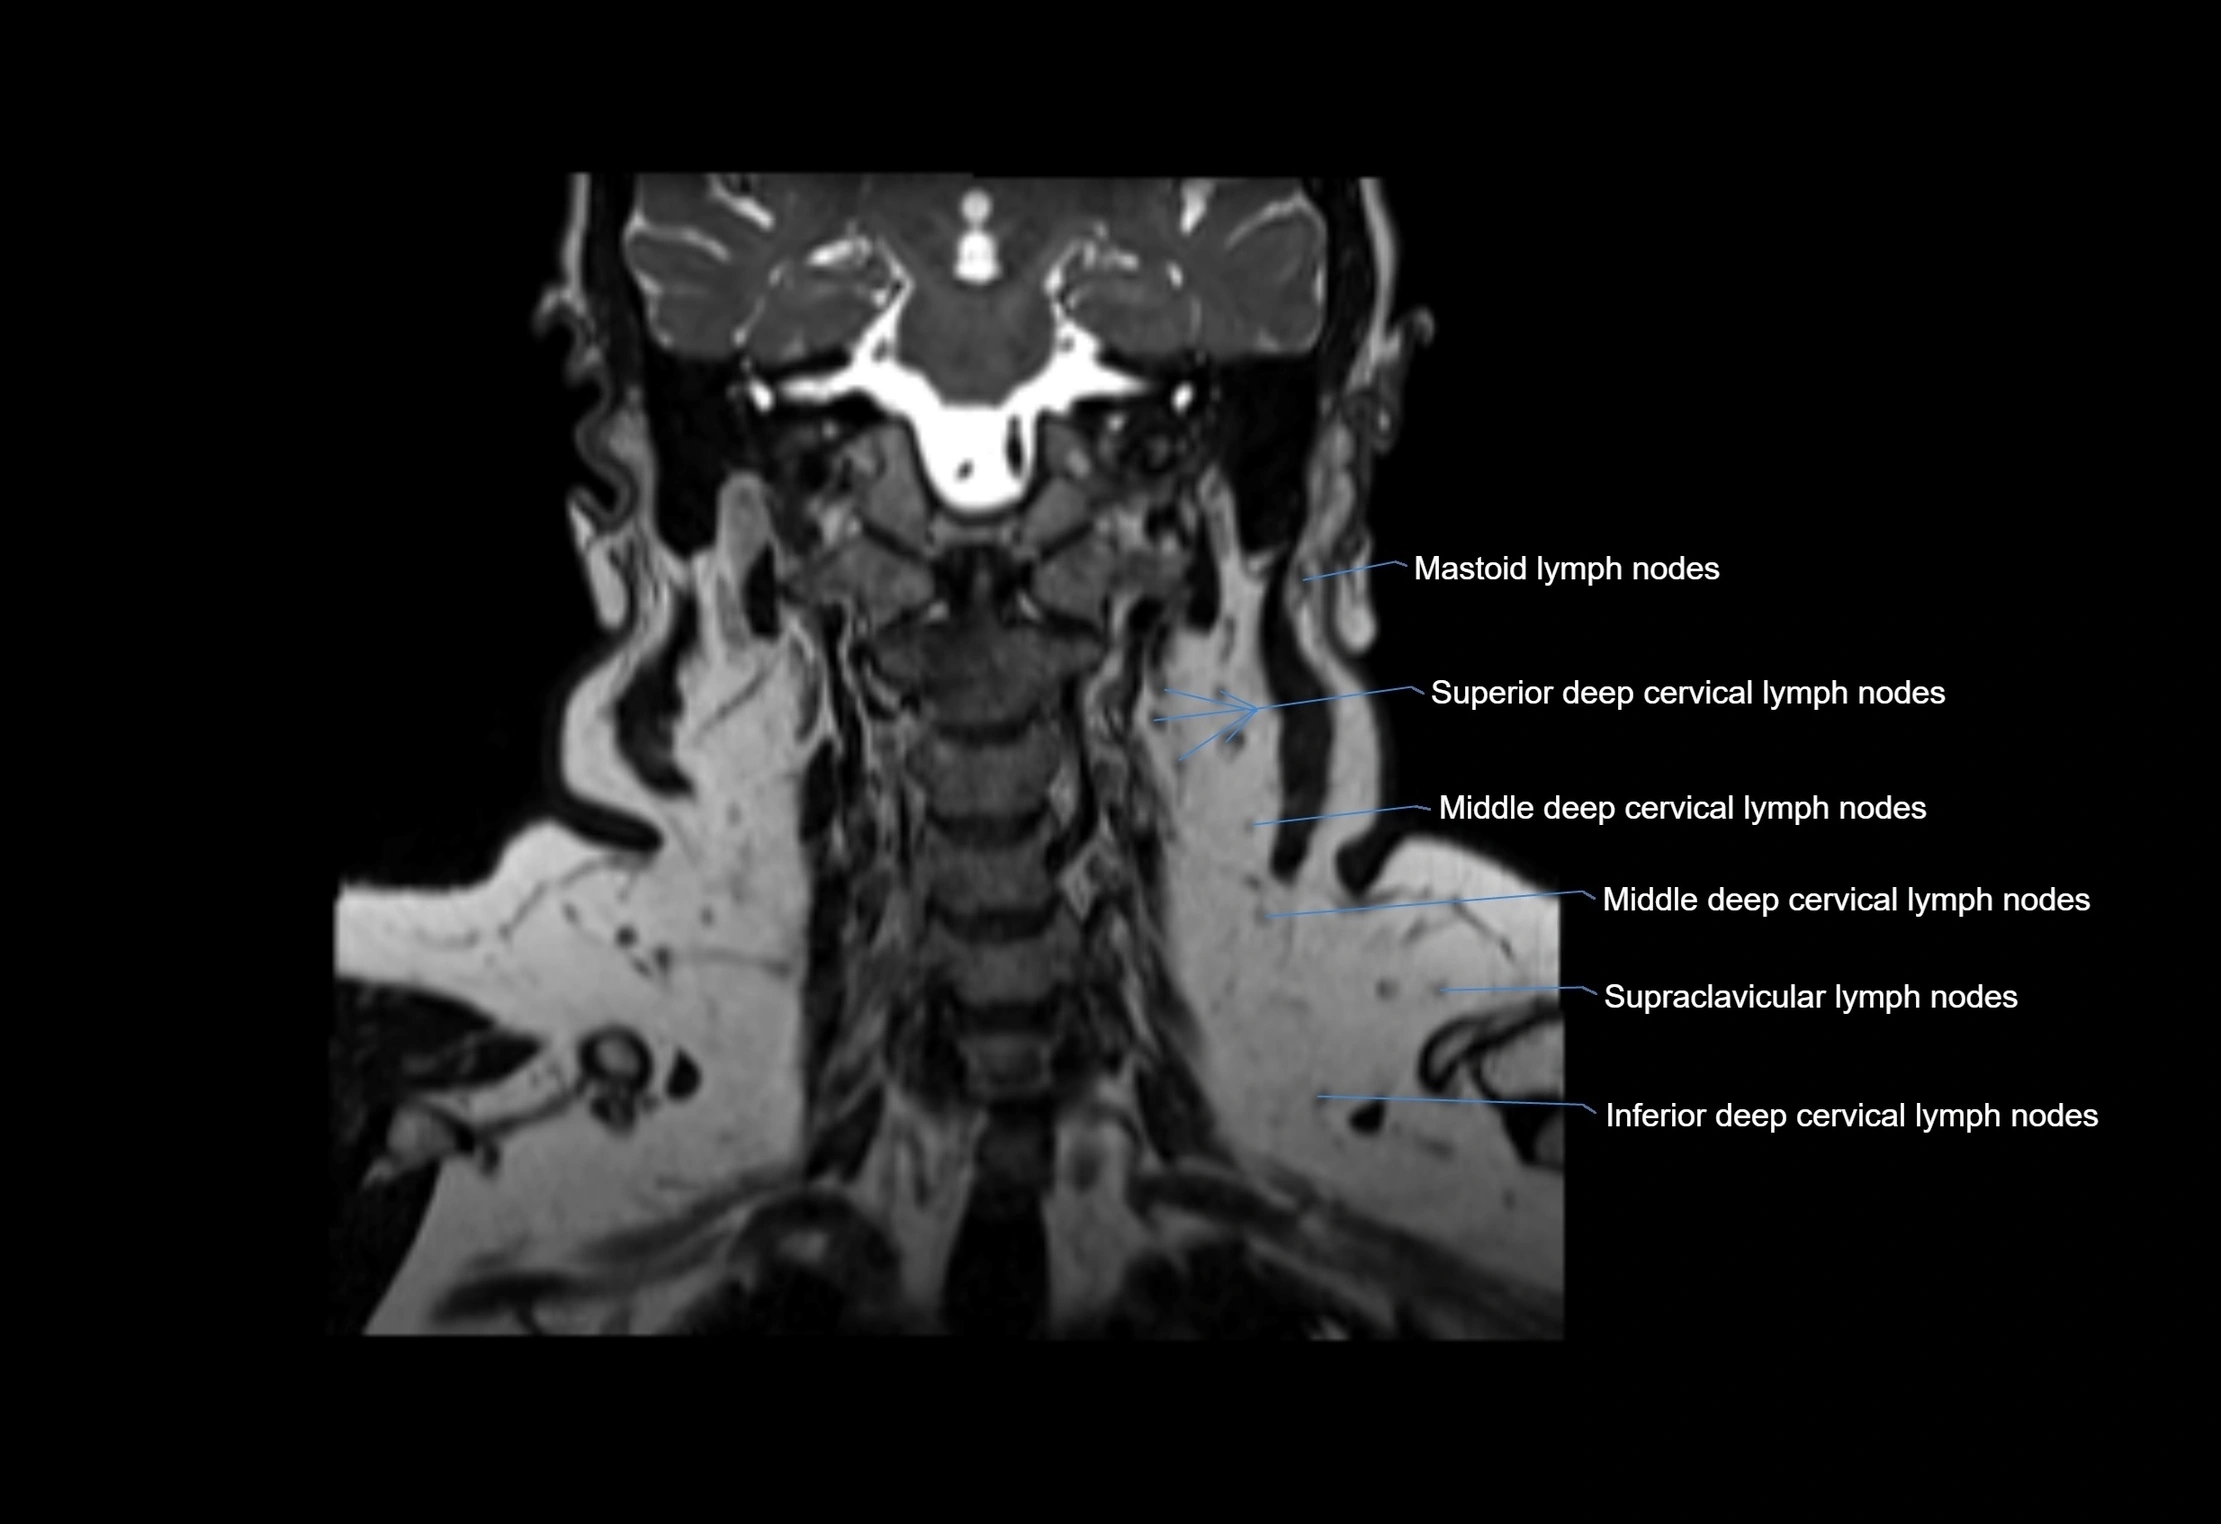

MRI images

image